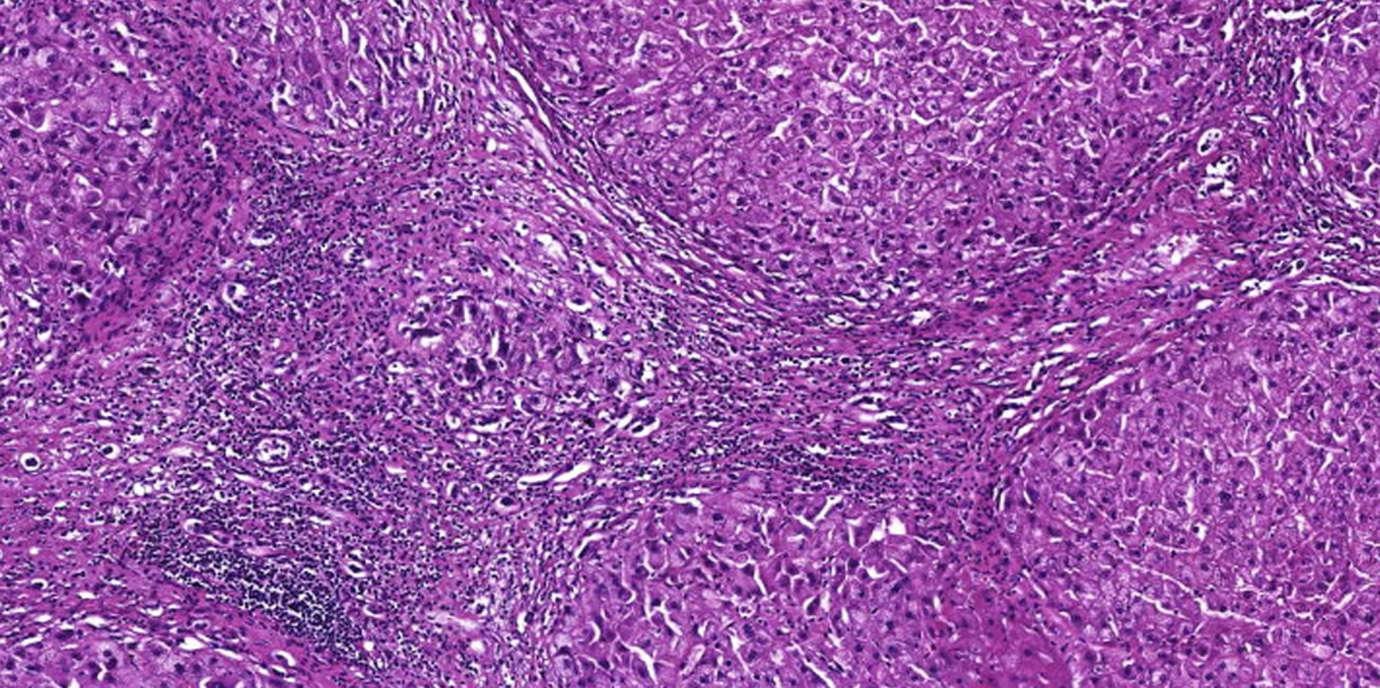

(28.11.2019, Doris Heidegger, Bild: V. Wieser)